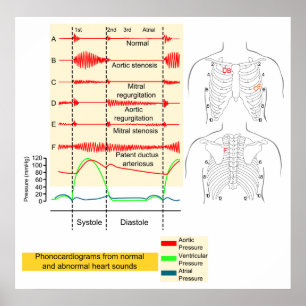

Cardiovascular Medical Diagram Poster

PriceCA$46.80